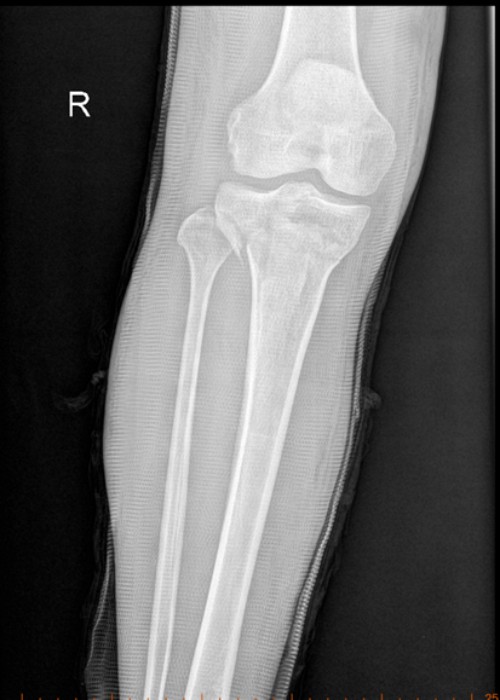

患者尚某因车祸致胫骨上段及胫骨平台骨折入院。此类骨折致残率极高,常规治疗多选择手术以降低致残风险,但尚某基础病情复杂,且家属明确拒绝手术。经骨科主任国华组织科室讨论,决定采用闭合手法复位结合石膏外固定方案,随后,国华与李泰锋医师为其实施精准手法复位,复查显示骨折端对位对线良好。目前患者恢复良好,家属对治疗效果表示高度认可。

复位后